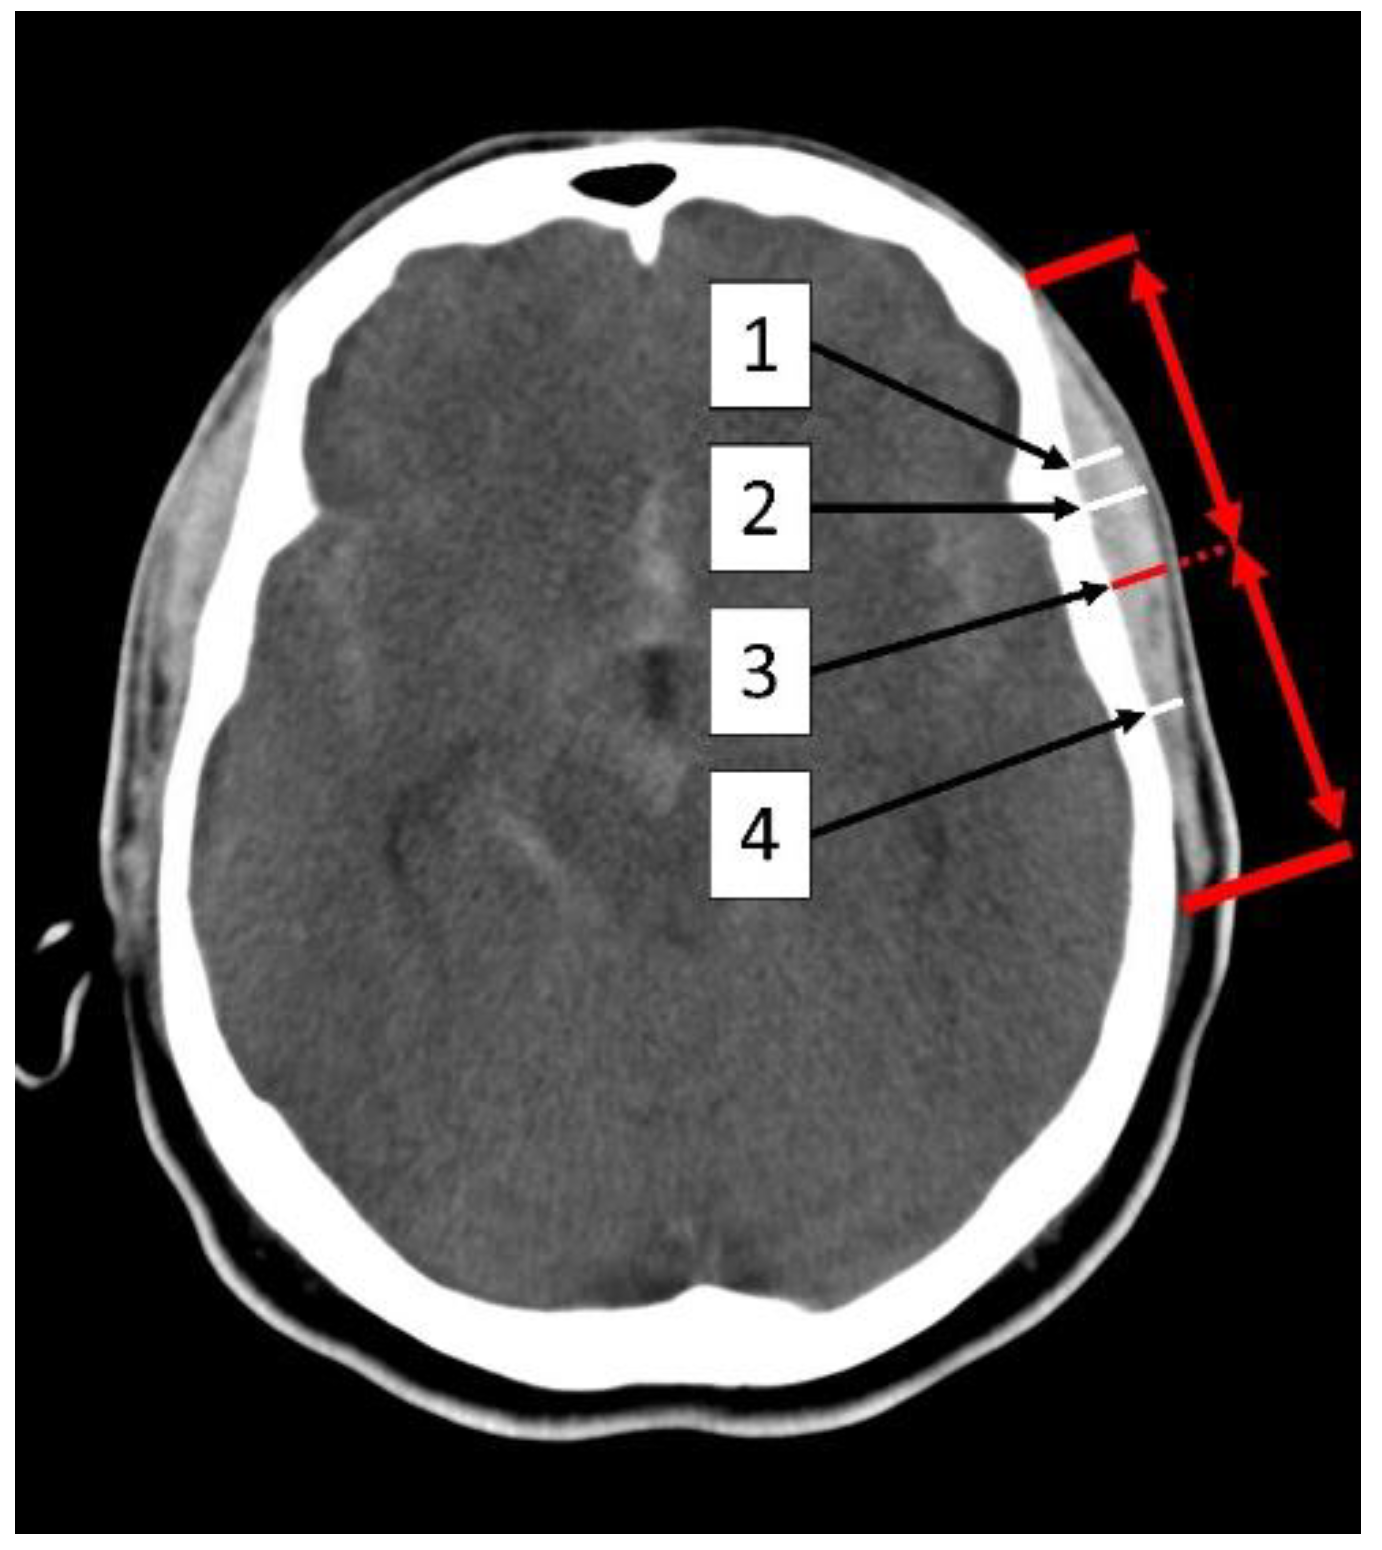

2.2. Measurement of the Temporal Muscle